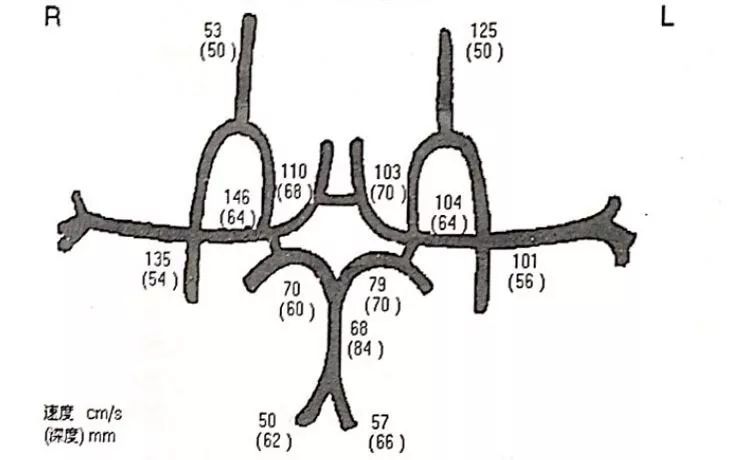

↑↑↑TCCD提示:同侧颈内动脉颅内段、大脑中动脉无狭窄。